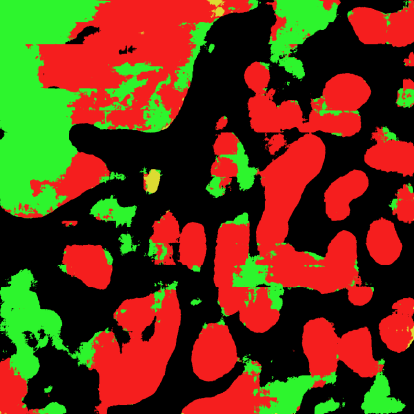

Pathologists diagnose and grade prostate cancer by examining tissue from needle biopsies on glass slides. The cancer's severity and risk of metastasis are determined by the Gleason grade, a score based on the organization and morphology of prostate cancer glands. For diagnostic work-up, pathologists first locate glands in the whole biopsy core, and -- if they detect cancer -- they assign a Gleason grade. This time-consuming process is subject to errors and significant inter-observer variability, despite strict diagnostic criteria. This paper proposes an automated workflow that follows pathologists' \textit{modus operandi}, isolating and classifying multi-scale patches of individual glands in whole slide images (WSI) of biopsy tissues using distinct steps: (1) two fully convolutional networks segment epithelium versus stroma and gland boundaries, respectively; (2) a classifier network separates benign from cancer glands at high magnification; and (3) an additional classifier predicts the grade of each cancer gland at low magnification. Altogether, this process provides a gland-specific approach for prostate cancer grading that we compare against other machine-learning-based grading methods.